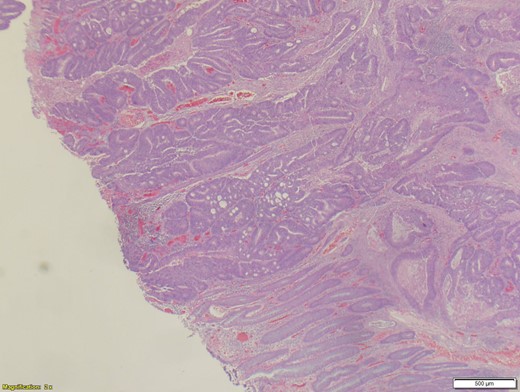

A 70-year-old female presented to the emergency department with complaints of diarrhea, vague, dull abdominal pain, unintentional weight loss and poor appetite. No hematochezia or melaena stated. Fecal occult is strongly positive in the ED. No endoscopies were found in her records. PMHx included COPD, osteoarthritis and DVT. Significant physical exam findings included mild, diffuse abdominal tenderness and RUQ palpable mass, and normal bowel sounds. Labs were significant for a hemoglobin of 5.7, hematocrit of 18.6% and CEA of 29.6. An abdominal/pelvis CT exhibited a 6 cm circumferential mass of the hepatic flexure (Figs 1–3). Two days later, a right hemicolectomy with en bloc pancreaticoduodenectomy was performed. Pathology showed adenocarcinoma stage IIIc (Figs 4–10). Post-operatively, an abdominal/pelvis CT showed bilateral pulmonary emboli and a 14 cm pelvic abscess. Bilateral lower extremity ultrasound showed low probability for DVT. Exploratory laparotomy was performed where the pelvic abscess was seen and extensive lysis of adhesions, resection of ileocolonic anastomosis for contained leak and ileostomy performed. Approximately 4 months after discharge, the patient passed away while in a long-term care facility.